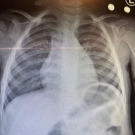

A 15-month-old boy presented to the emergency department with multiple episodes of vomiting and a subjective fever for 2 days.